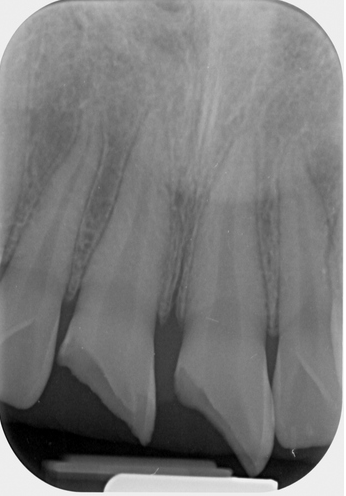

7歲孩童小松是在一年半前不小心把上顎新萌發的恆齒撞斷,經急診醫師會診根管治療科賴博堂主任接手以活髓治療。現在的小松雖然偶爾會因咬到堅硬的食物而使黏上去的斷片掉落,需再重新黏上之外,整顆牙仍保留恆齒成長潛能。

右圖:7歲孩童小松是在一年半前不小心把上顎新萌發的恆齒撞斷,圖為術前X光影像。(賴博堂提供)